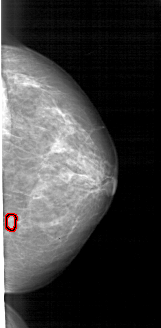

A_1715_1.LEFT_CC

LEFT_CC LINES 4861 PIXELS_PER_LINE 2371 BITS_PER_PIXEL 12 RESOLUTION 43.5 NON_OVERLAY

FILE: A_1715_1.RIGHT_CC.OVERLAY

TOTAL_ABNORMALITIES 1

ABNORMALITY 1

LESION_TYPE MASS SHAPE LOBULATED MARGINS OBSCURED

ASSESSMENT 3

SUBTLETY 3

PATHOLOGY BENIGN

TOTAL_OUTLINES 1

BOUNDARY